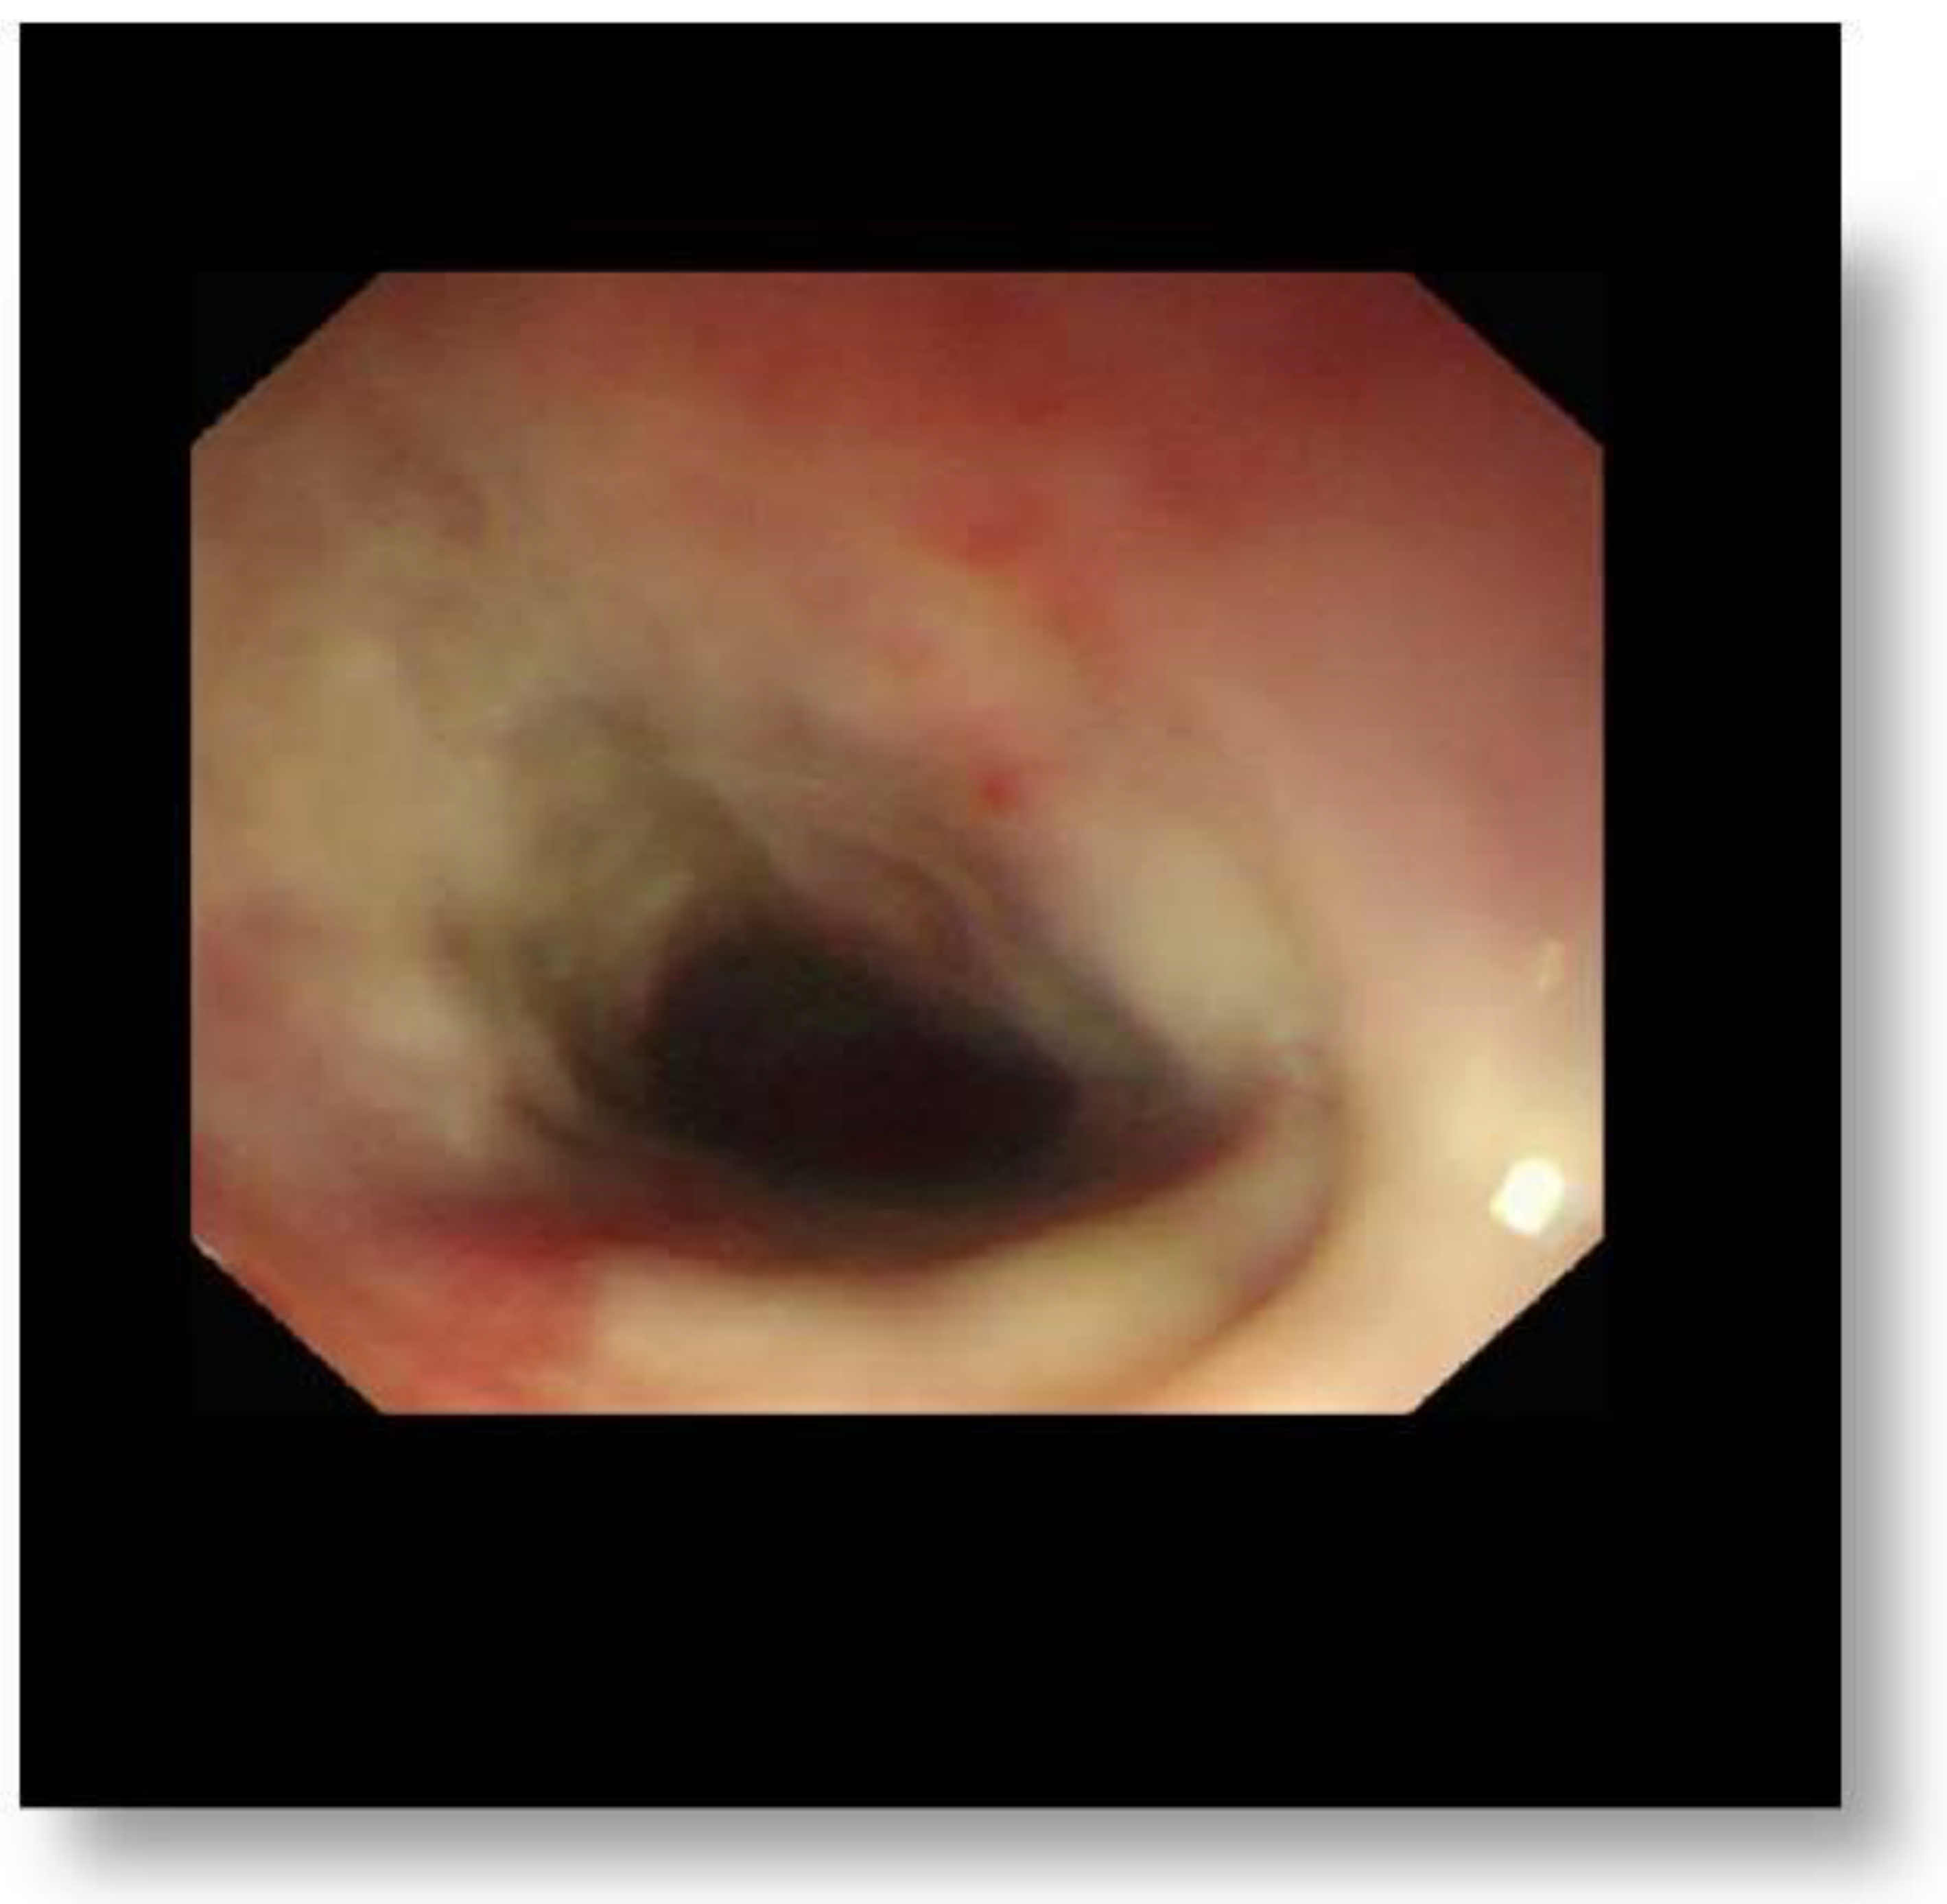

The majority of complications (such as malnutrition) were noticed in children with grade 3A injuries. In consequence, prolonged hospitalization has been required. The second endoscopy (done six months after ingestion) revealed stricture as the most common late complication (n = 13, 60.60%: 8 patients with grade 2B (Figure 1) and 5 with grade 3A) (Table 3). None of our patients developed perforation.

Figure 1. Stricture as the most common late complication.